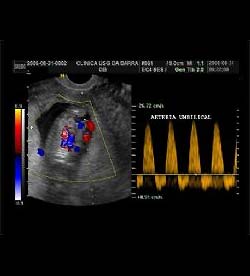

Artéria Umbilical

Durante o primeiro trimestre da gestação, a presença de diástole zero no sonograma-doppler da artéria umbilical, faz parte de processo normal.

Porém a presença de diástole reversa (como na figura) no sonograma-doppler da artéria umbilical em gestação de primeiro trimestre é achado anormal, correlacionando-se com risco aumentado de cromossomopatia fetal.